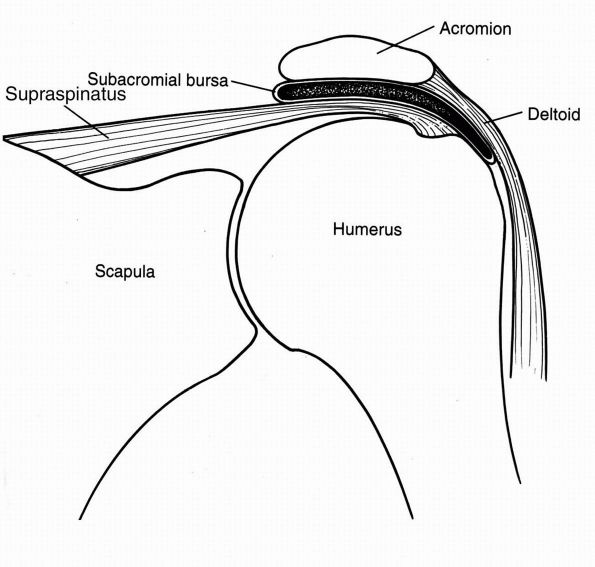

compression of the rotator cuff between the unyielding surfaces of the

humerus and coracoacromial arch, which is composed of the coracoid,

coracoacromial ligament, and the anterior acromion (Figure 12-21). Inherent morphologic variations of the acromion (flat, curved, or hooked) (Figure 12-22)

or age-related acromial spur formation may contribute to the role of

mechanicalbased pathology of the rotator cuff. Biomechanical

analysis

has demonstrated a correlation between a hooked acromion and increased

contact with the underlying cuff. Furthermore, contact of the acromial

undersurface has also been shown to occur predominantly with the

supraspinatus, consistent with the majority of pathology originating in

this location. More recent studies have described the entity of